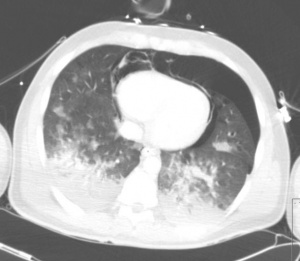

CT scan showing pneumopericardium with pneumomediastinum, pneumothorax, hemothorax, and pulmonary contusion after severe chest trauma[1]

[[File:Pneumothorax hemothorax pneumomediastinum contusion.jpg|thumb|CT scan showing pneumopericardium with pneumomediastinum, pneumothorax, hemothorax, and pulmonary contusion after severe chest trauma<ref>Konijn AJ, Egbers PH, Kuiper MA (2008). "Pneumopericardium should be considered with electrocardiogram changes after blunt chest trauma: a case report". J Med Case Reports. 2 (1): 100. doi:10.1186/1752-1947-2-100. PMC 2323010. PMID 18394149.</ref>]] | [[File:Pneumothorax hemothorax pneumomediastinum contusion.jpg|thumb|CT scan showing pneumopericardium with pneumomediastinum, pneumothorax, hemothorax, and pulmonary contusion after severe chest trauma<ref>Konijn AJ, Egbers PH, Kuiper MA (2008). "Pneumopericardium should be considered with electrocardiogram changes after blunt chest trauma: a case report". J Med Case Reports. 2 (1): 100. doi:10.1186/1752-1947-2-100. PMC 2323010. PMID 18394149.</ref>]] | ||